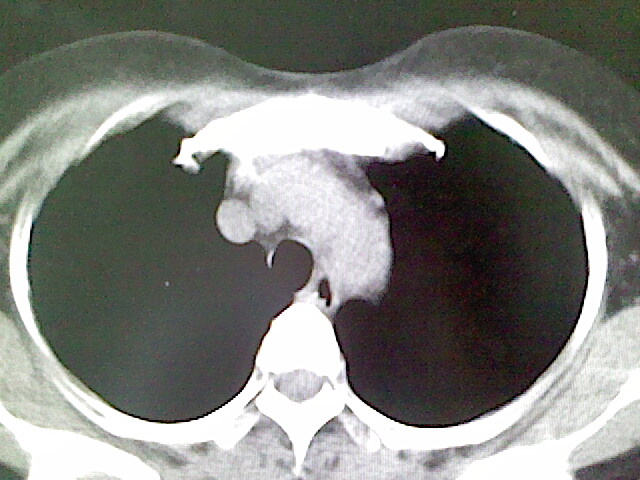

女,52岁,咳嗽,咳痰多日

左下肺陈旧纤维索条!

左肺舌段炎性改变

我见过几例,为炎症后纤维条索

慢性炎症后改变

考虑慢性炎性病灶粘连牵拉改变。

左肺舌叶纤维锁条病变。

左肺上叶下舌段炎症并局部胸膜反应。

左肺舌叶纤维索条影。

左肺舌叶段陈旧性病变

左肺舌段炎性反应。片子的质量太不好了。

左肺舌段炎性

炎性改变

左肺舌叶纤维索条影